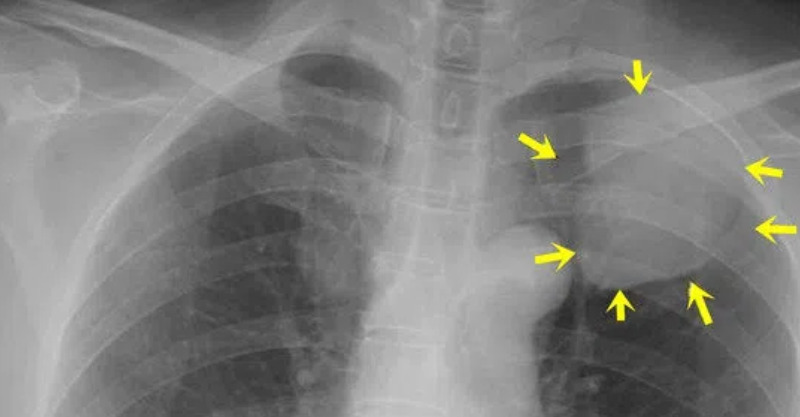

難以發覺的「早期肺癌」

但讓人惋惜的是,肺癌一經發現往往已屬中晚期,給患者和家庭帶來很多痛苦。

這是因為,早期肺癌與普通感冒、上呼吸道炎症以及肺部輕度炎症相類似,很容易被疏忽。

當腫瘤發展到一定程度,才會出現與普通疾病不同的特殊癥狀,如刺激性咳嗽、痰中帶血絲、胸悶胸痛、氣促、發熱、身體明顯消瘦等癥狀,但此時肺癌往往已進展到中晚期,甚至有些已失去了手術機會。